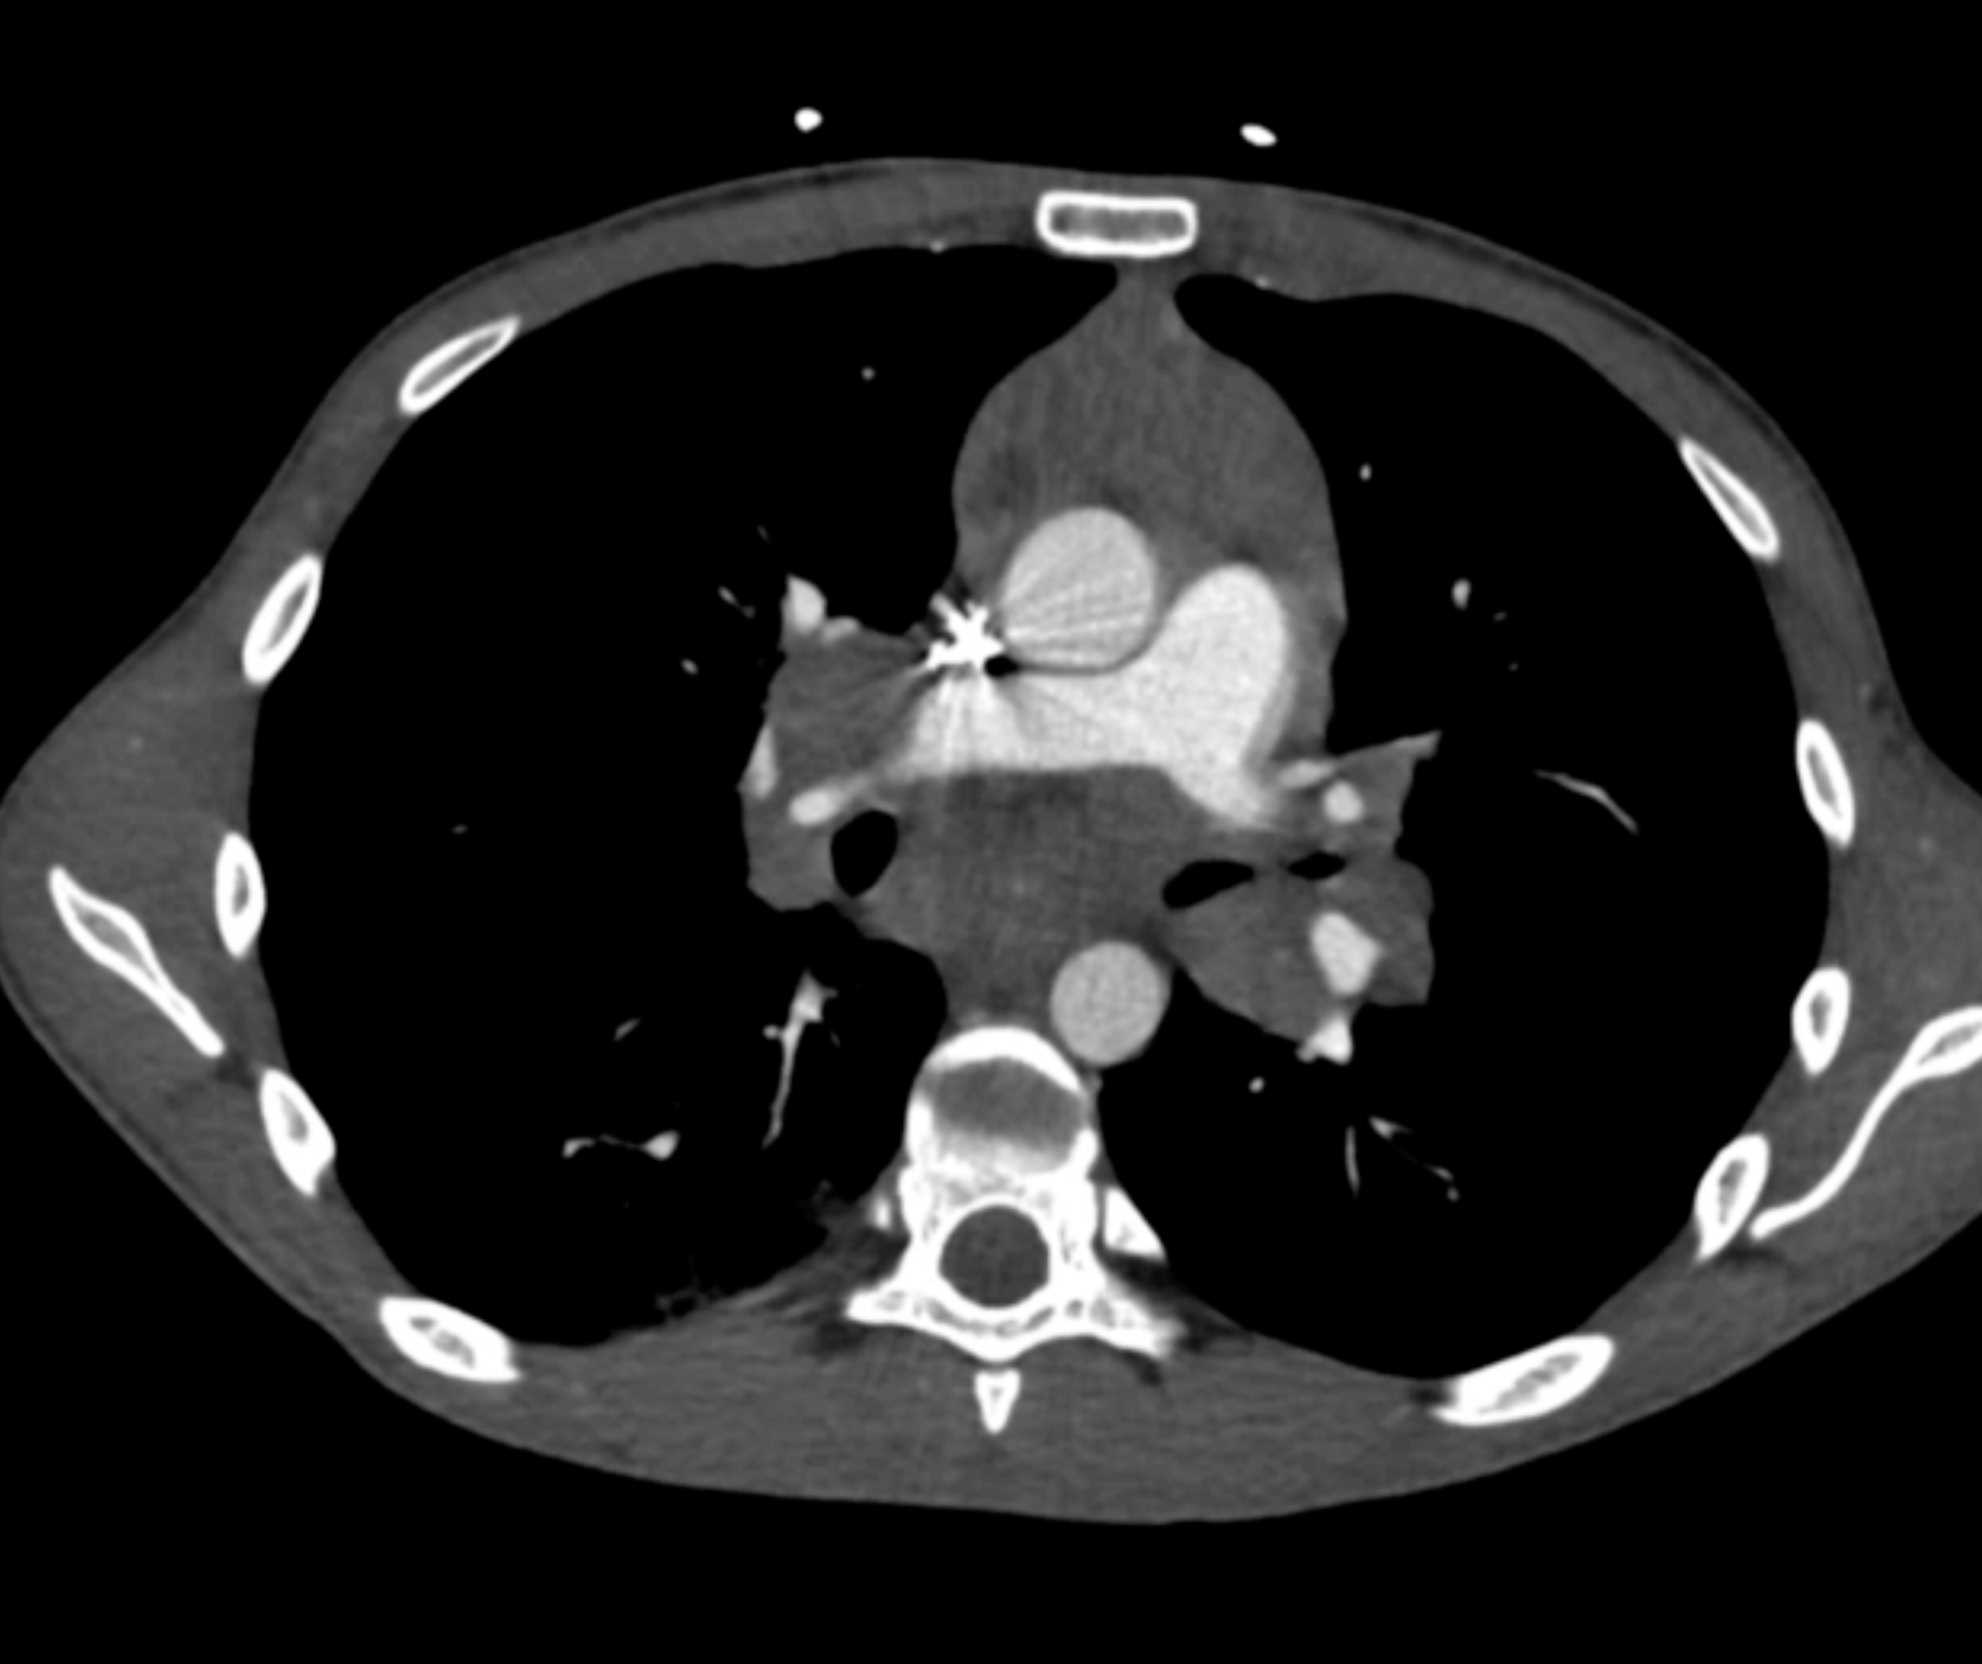

Large Cell Lymphoma